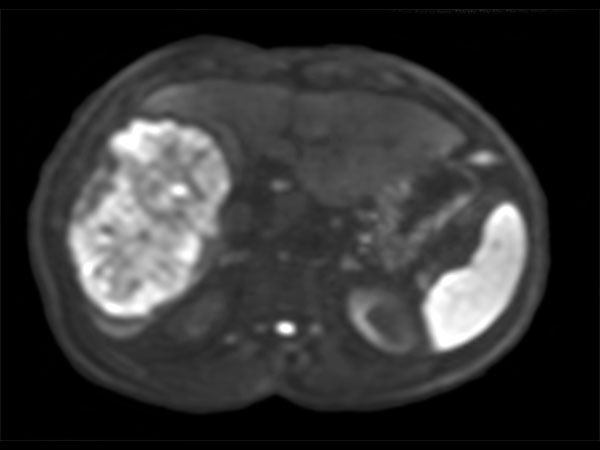

62 year old patient with huge, non-cirrhotic liver tumor. Question is if the portal vein is closed or not which has a direct influence on treatment options. Portal vein turned out to be open and patient was referred for embolization. No other tumors / lesions were found.

Axial Diffusion (b1200)